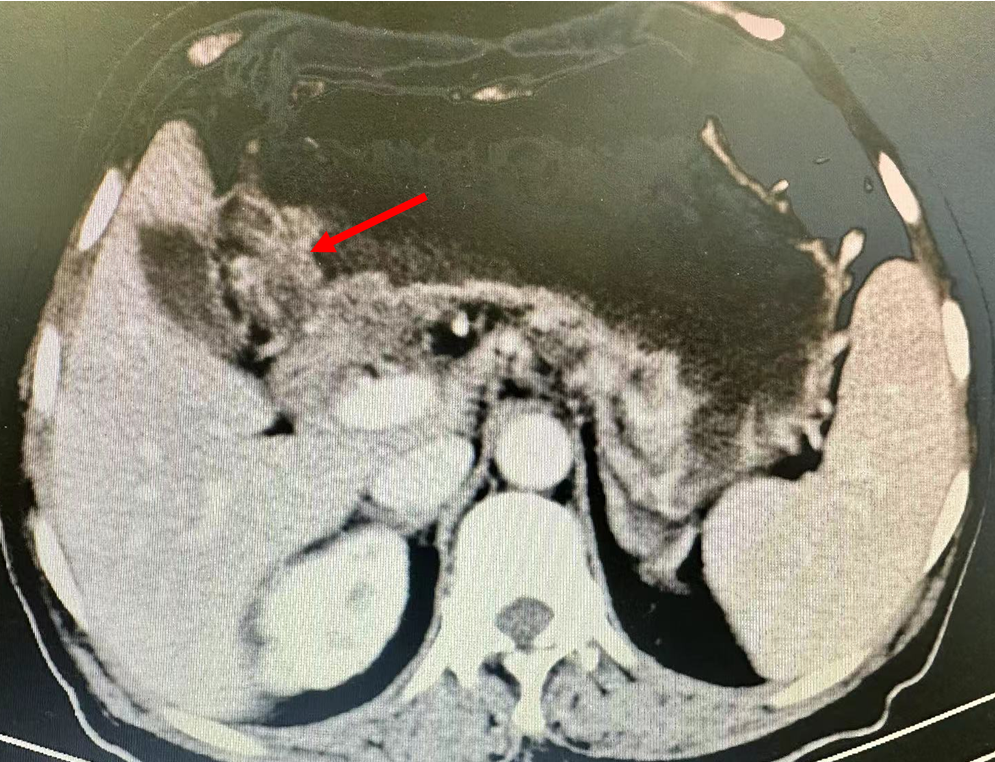

术前胃CT图,箭头指示胃窦增厚

患者为52岁女性,患者5月前无明显诱因下出现呕吐,为胃内容物,伴食欲不振,无腹痛腹泻,无畏寒发热,无咳嗽咳痰,无胸闷气促等不适。遂至当地医院就诊,查胃镜提示:胃窦占位。进一步胃镜病理提示:中分化管状腺癌。增强CT提示胃窦增厚,伴胃周多发淋巴结转移,转至上海某医院就诊,予以6次化疗及免疫治疗,方案:雷替利珠单抗+CapOX。化疗后行CT检查提示:胃周淋巴结治疗后缩小,评价PR。患者自起病来精神可,胃纳差,二便如常,体重无明显增减。经MDT讨论,认为患者新辅助治疗后,肿瘤评价PR,拟行腹腔镜远端胃切除术。